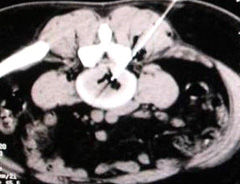

1)SCS(脊髓電刺激)技術

有關SCS鎮痛作用機制仍然還在探討中。目前認為可能與下列學說有關:

①閘門控制理論

②脊髓-丘腦通路傳導阻斷理論

③脊髓上痛覺調控神經元系統激活理論

④交感神經系統相關中樞性抑制理論

⑤中樞遞質系統平衡改變理論